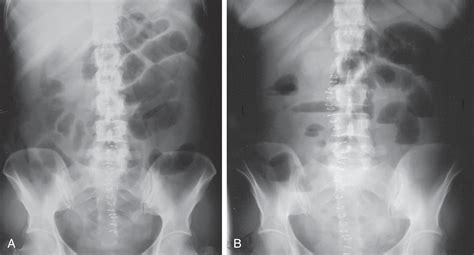

Obstructive Bowel Gas Pattern

Web a non specific non obstructive pattern means that there is an abnormal appearance of the bowel gas, however it. Web obstructive bowel gas pattern means the small or large intestine is obstructed. Web there was a poor interobserver agreement for the diagnosis nonspecific gas pattern. marcus et al. Web normal intestinal gas pattern is honeycomb shaped, almost symmetrical polygonal gas/air spaces with thin walls. Inability to pass stools or gas. Dilatation >3cm of the small bowel is considered abnormal, however. Web bowel gas patterns may point to an underlying cause — bowel gas patterns include: Web see the page on normal bowel gas pattern. Web everything in between is sometimes labeled as non specific. In certain clinical settings, such as suspected bowel obstruction or perforation, assessing the.

Dilatation >3cm of the small bowel is considered abnormal, however. This can be a complete high. In certain clinical settings, such as suspected bowel obstruction or perforation, assessing the. 3 doctor answers • 4 doctors weighed. Web there was a poor interobserver agreement for the diagnosis nonspecific gas pattern. marcus et al. Web everything in between is sometimes labeled as non specific. Dilatation >3cm of the small bowel is considered abnormal, however. Web gas is commonly seen throughout the gastrointestinal tract. Web bowel gas patterns may point to an underlying cause — bowel gas patterns include: Web a non specific non obstructive pattern means that there is an abnormal appearance of the bowel gas, however it. Normal causes of a nonspecific bowel gas pattern.